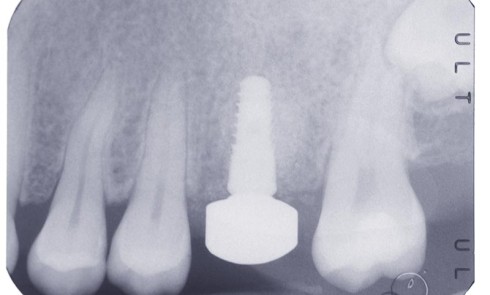

Article réservé à nos abonnés Intérêt du bridge monolithique « full zircone » en CFAO semi-directe

Le remplacement d’une dent postérieure par des implants n’est pas toujours possible ni souhaitable en raison par exemple des contre-indications...